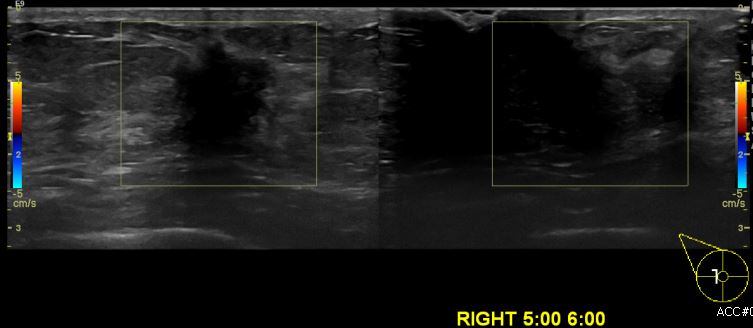

상기환자 건강검진상 이상소견으로 내원하신 60대 여성분으로 우측 5시~6시 방향

의심스러운 멍울 조직검사 시행하여 우측 침윤성 유관암 진단 되었습니다.